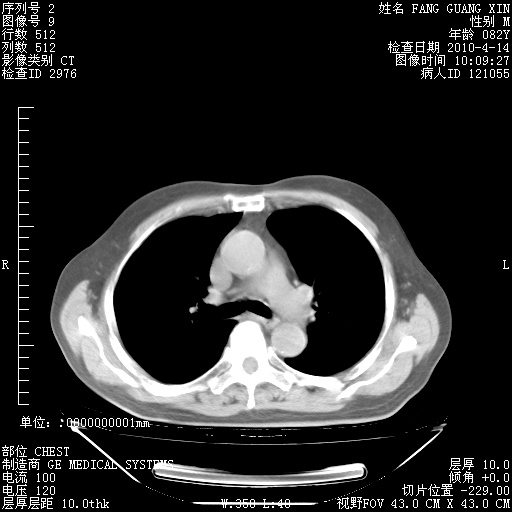

肺部CT平扫未见异常。